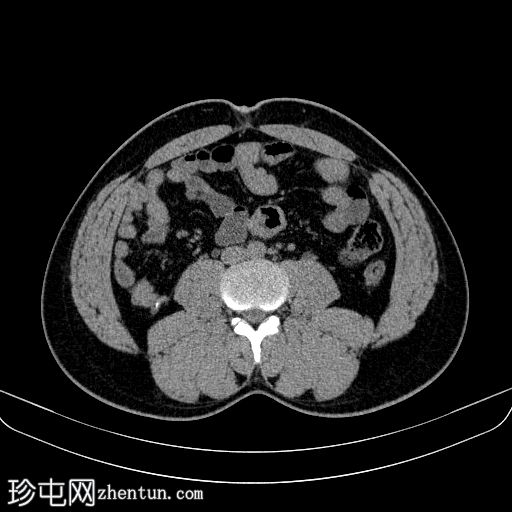

轴位

平扫

双侧肾结石,无梗阻,较大结石位于左侧肾下盏,最大直径约4 mm,平均CT值约730 HU,伴左侧输尿管轻度扩张。

膀胱明显充盈,高度达脐部,若患者无法排尿,可能需要导尿。

患者主诉左侧肾绞痛,既往有肾结石病史。